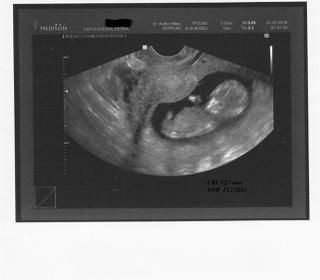

Leni děkuji, mám strach aby mu nepřestalo srdíčko tlouct a nevzdál to! ☹ Vím, že už vypadnout nemůžou, už mají přece i kostíky! 😵 Každým týdnem študuji co se dějě a co se vyvýji. 😵 Jen to srdíčko! 😖 Snad bude vše ok! Zítra určo pošlu fotečku i fotečku průkajdy!

Ahoj holky! Tak jsem dnes byla na UTZ, ale nedopadla jsem zrovna moc dobře. Doktor si nebyl jistý, zda je tam srdíčko, takže jdu zítra na do nemocnice na velký UTZ, který buď jeho domněnky potvrdí nebo vyvrátí. Jsem z toho hoooodně špatná. Možná se s Vámi v této kolonce loučím, ale díky za dosavadní podporu. My už na další IVF nepůjdeme, já na to nemám sílu a mražáčky taky nemáme. Tak se mějte, zítra dám ještě vědět. Pa. M.

O 12ej sme mali kontrolu. UTZ nerobila Dr., vraj až o týždeň v Gennete, teraz by to bolo zbytočne. Len mi prezrela maternicu a vraj sliznica je oki, tak sa nemám báť - včera som opäť totiž večer trošku zašpinila. Dr. tvrdí, že je to po IVF normál. Takže normál len tlak, moč, krv, cyt. som mala pred IVF takže rovnako nerobila, no a následne 8.7. NT v Gennete a u Dr. sa uvidíme až 2.8. Čo je krásne, dostala som tehu preukážku, je to dosť veľké, nosíte to všade so sebou?? Ale nevadí, ak sa musí, hlásim sa teda ako oficiálna tehulka 🙂

@marmar79 - nie je to určite nič príjemné, ale nebaľ to, uvidíš, čo Ti povedia, možno sa srdiečko uvidí až v 10. tt.. ja som ho mala koncom 9eho - začiatkom 10eho.. rieš to, keď to bude isté. Držím palečky 🙂

petulke ta fotka je naprosto úžasná 🙂